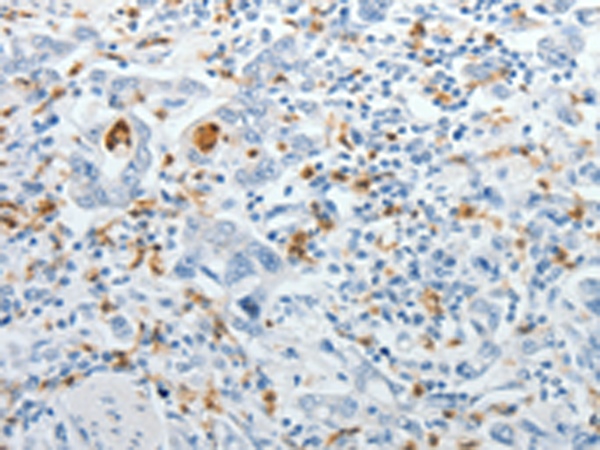

分类: 科研抗体货号: P11119别名: NPTIIb, NAPI-3B, NAPI-IIb应用: IHC反应种属: Human